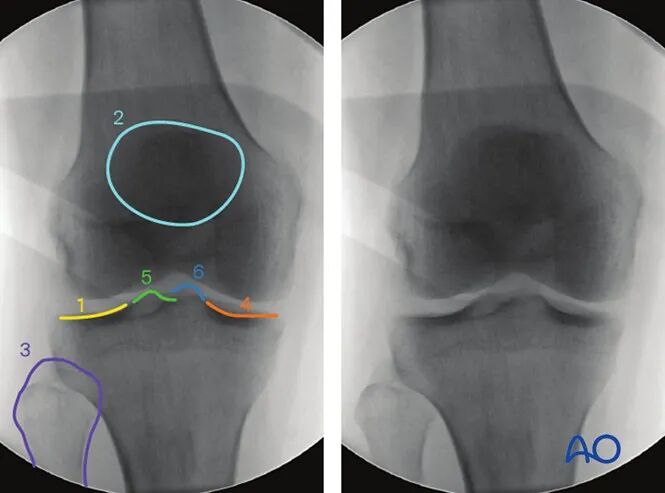

4. 胫骨近端10°头倾前后位

最佳体位摆放要求

以标准前后位为基础体位,

将C臂机向尾侧倾斜,直至清晰显示胫骨真实关节面,倾斜角度约为10°。

最佳影像的验证标准

满足以下条件即为胫骨真实关节面的最佳影像:

●胫骨关节面居中显示于影像屏幕;

●内侧与外侧关节面线影完全重合。

可识别的解剖标志与线条

该体位下可识别的解剖标志与线条包括:

1.外侧胫骨平台(凸面线影)

2.内侧胫骨平台(凹面线影)

3.内外侧胫骨棘

4.骨骺线瘢痕。

临床观察要点

该体位尤其适用于判断以下情况:

●关节面复位不良;

●关节内植入物位置;

●关节面与胫骨长轴的夹角是否正常(正常范围85°-90°)。